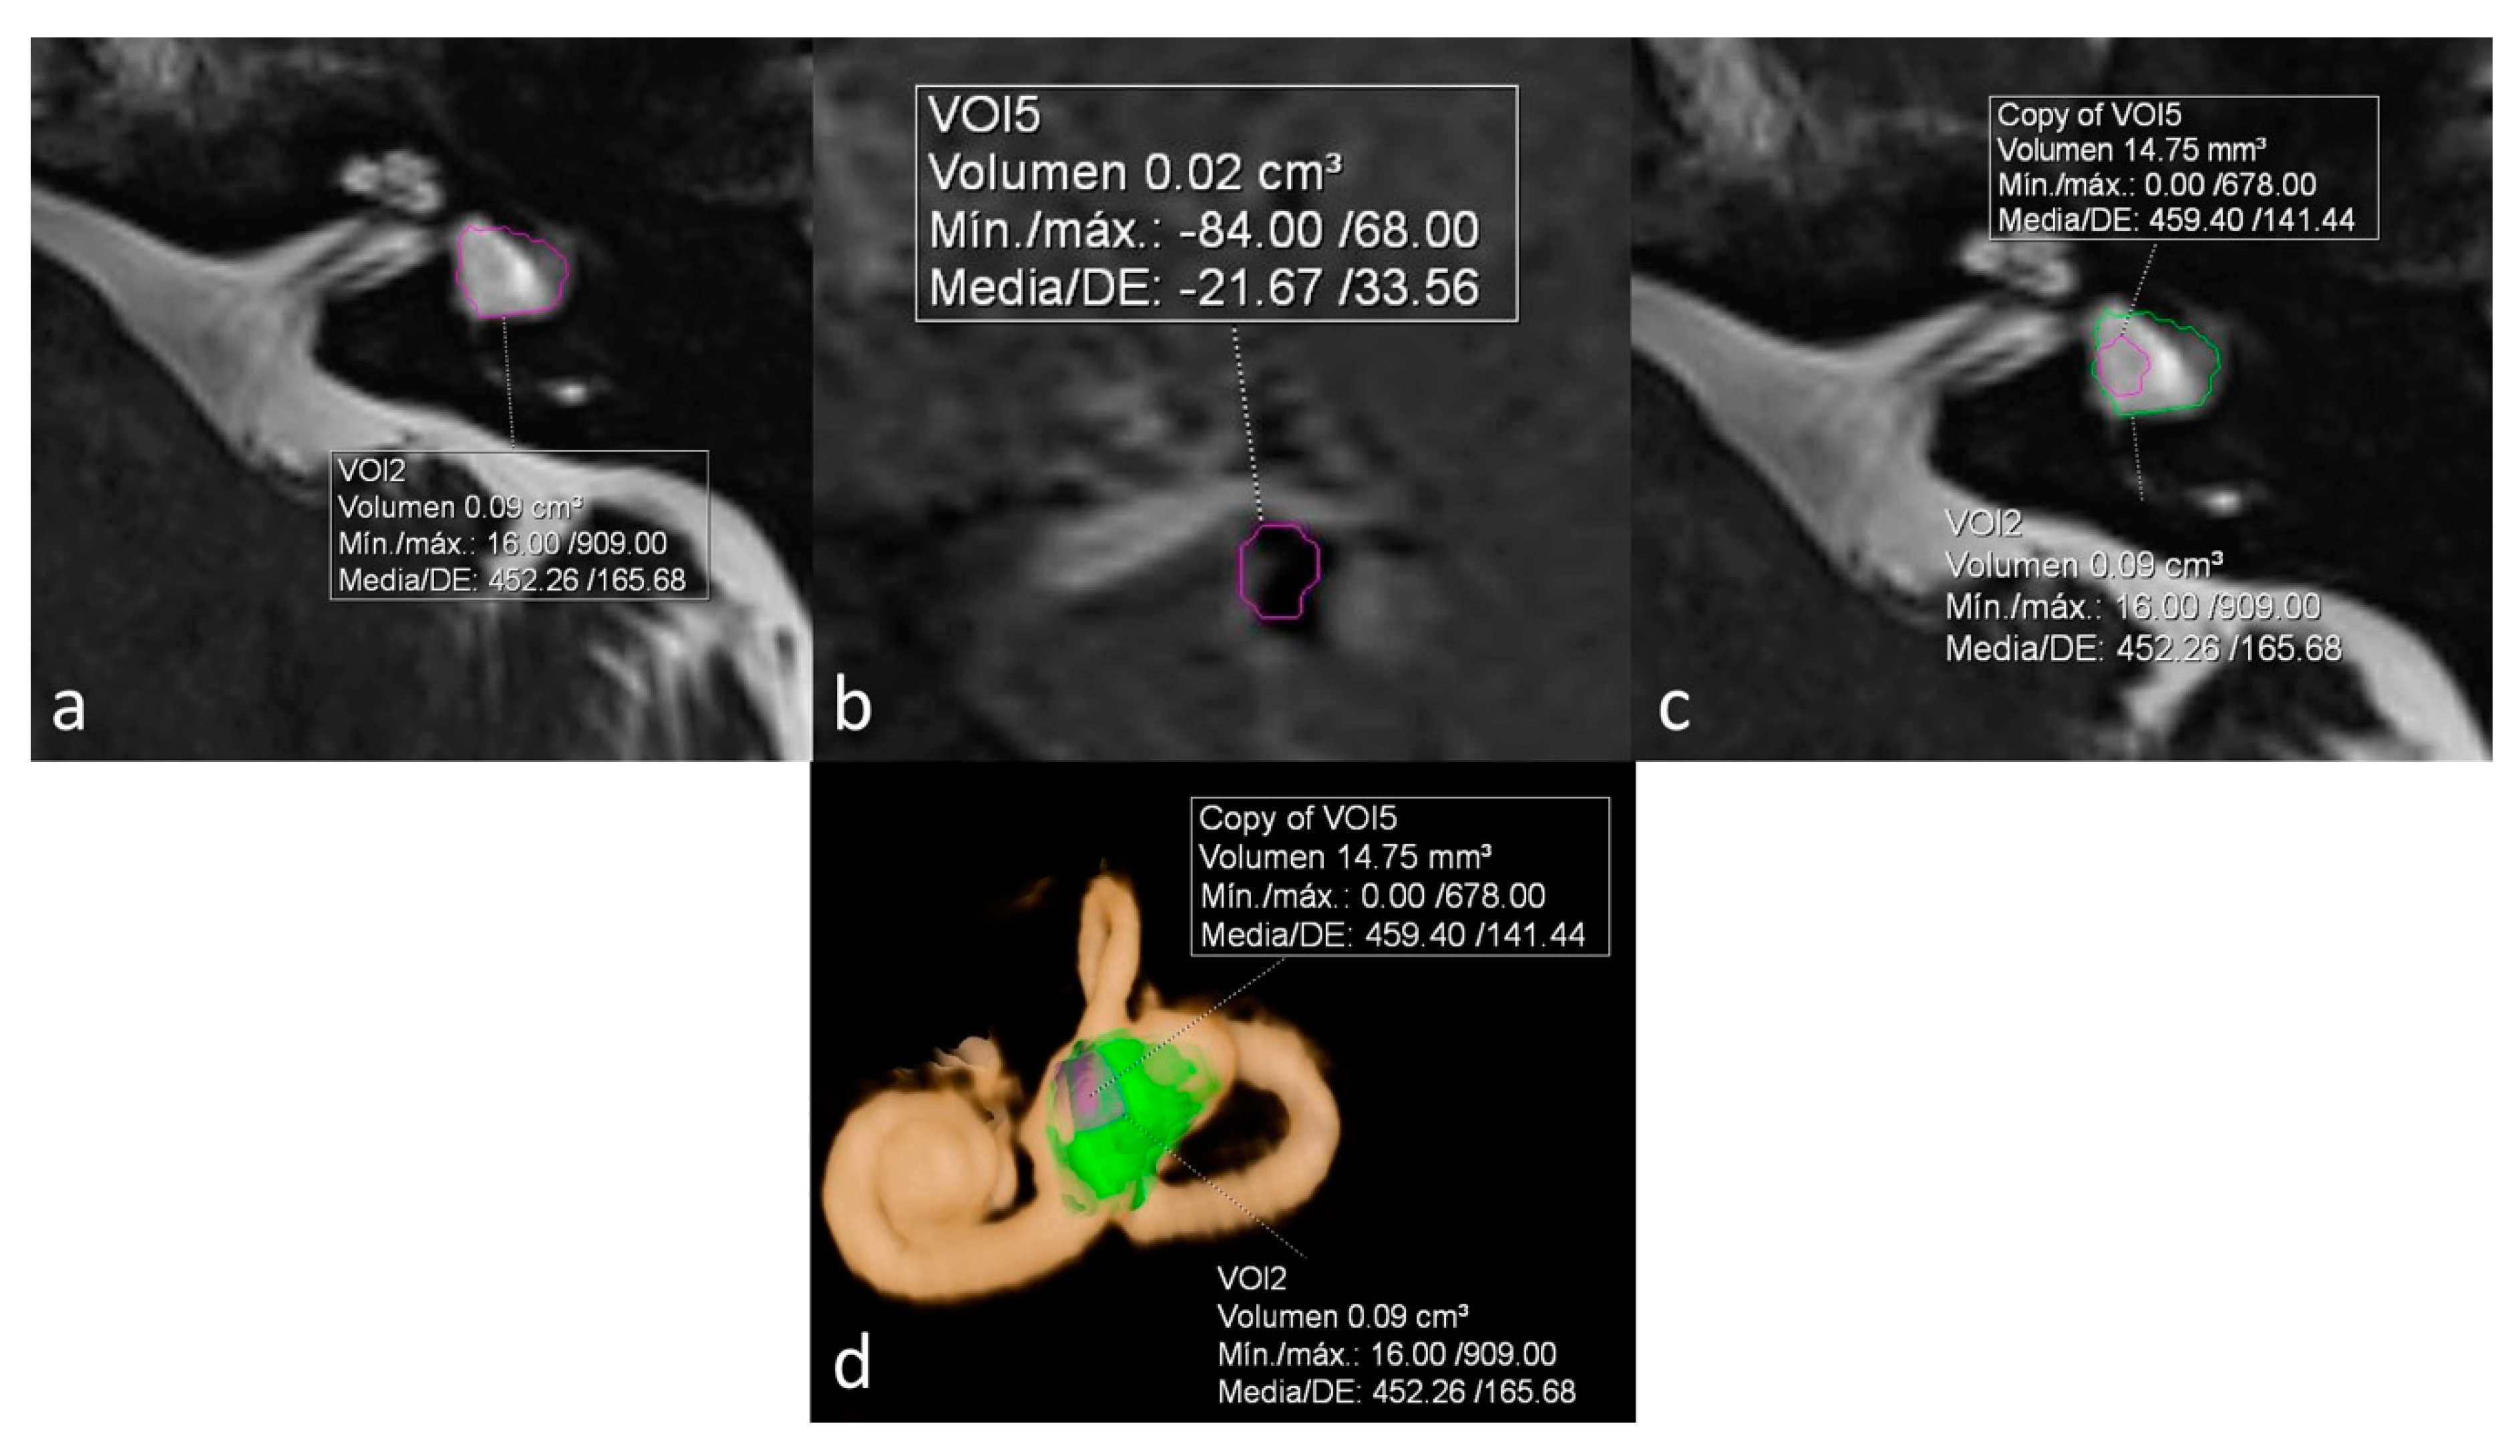

ELR ranged from 22% to 81%. It´s interesting to note that both extremes were present in the same patient, corresponding to a patient with right unilateral Ménière’s syndrome but with bilateral LSCCD (patient 4). On the dysplastic clinically affected side, ELR was 81% (Figure 2), whereas on the dysplastic clinically asymptomatic ear, ELR was barely 22% (Figure 3). In patients with unilateral LSCCD and available hydrops MR imaging (patients 3 and 5), the contralateral “normal anatomy” inner ear showed no signs of endolymphatic hydrops with endolymphatic ratios of less than 25% (not shown). The contralateral “normal anatomy” inner ear was asymptomatic.

Figure 3.

Same patient as in Figure 2. Left ear. No Ménièriform symptoms on this side. (a) Cisternography sequence showing LSCCD with volumetric measurement of total vestibular cavity volume. (b) 3D-IR-REAL sequence depicts volume of vestibular endolymph. (c) Overlay of both volumetric measurements in the cisternography image (d) 3D volume-rendered with color-coded volumes, obtaining an ELR of 22%, consistent with the lack of symptoms on this ear.